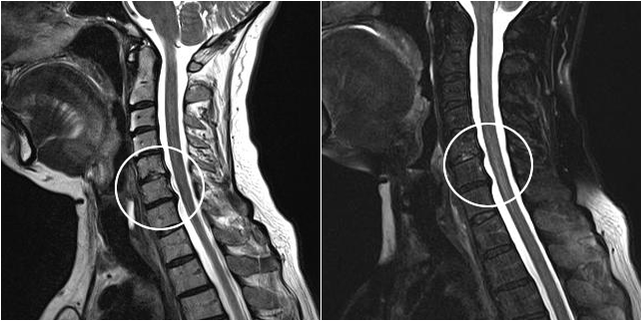

Οι σύγχρονες διαγνωστικές μέθοδοι περιλαμβάνουν μαγνητική τομογραφία και αξονική τομογραφία, οι οποίες καθιστούν δυνατή την ακριβέστερη μελέτη των διαδικασιών καταστροφής του χόνδρου και του οστικού ιστού. Αυτή η τεχνική μπορεί επίσης να χρησιμοποιηθεί για την εύκολη διάγνωση κήλης και άλλων ελαττωμάτων μαλακών μορίων κοντά στην πηγή της νόσου.

Αυχενική οστεοχονδρωσία σε εικόνα μαγνητικής τομογραφίας